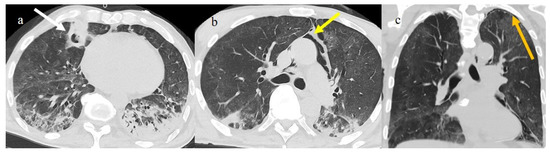

3.3.2. Pneumomediastinum and Pneumothorax

3.3.3. Pulmonary Fibrosis

3.3.4. Pulmonary Thromboembolism